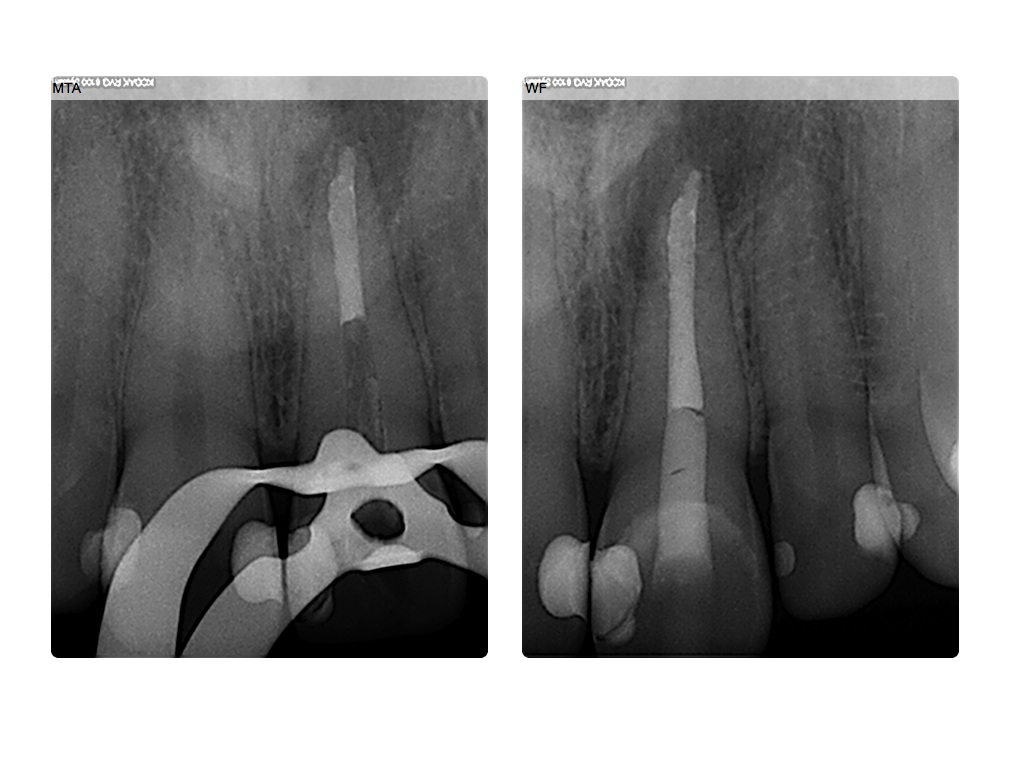

005-001 Veröffentlicht 13. Januar 2014 am 1024 × 768 in Hätten Sie es gesehen? (2) MTA und Abschlusskontrolle